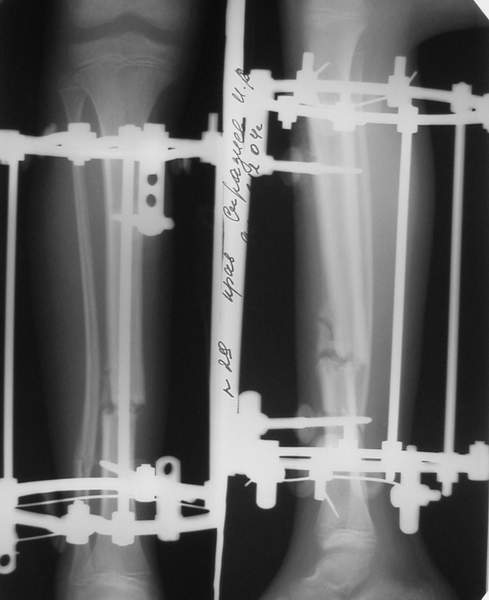

В аттачте № 3 - один из примеров полукольцевого аппарат...

Это уже я баловался.

Итог? Работы больше (по времени и

интраоп "подгонке"), срастается также, а особого преимущества по сравнению с

"чиста" кольцевым (вес, удобство ношения и пр.) - я, по крайней мере,

не нашел.

Теперь не балуюсь.

Может быть зря?

;-)